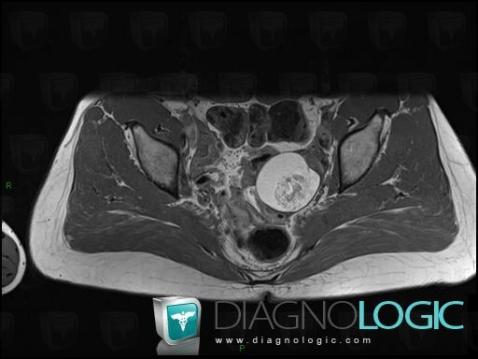

Teratoma, Pelvis / Perineum, MRI

Here is the specific information in the key image above:

- Diagnosis Teratoma (link to Dermoid cyst), Location(s) Pelvis / Perineum, with gamuts Fat containing pelvic mass, Complex pelvic mass